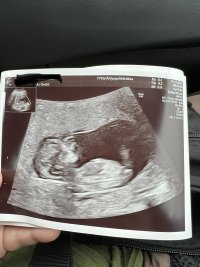

Oi, så tydelige bilderSer tydelig nub her. Men 11+2 og mål til 11+4, så skal de være like på gutter og jenter i noen dager tilVis vedlegget 419570

Vis vedlegget 419571